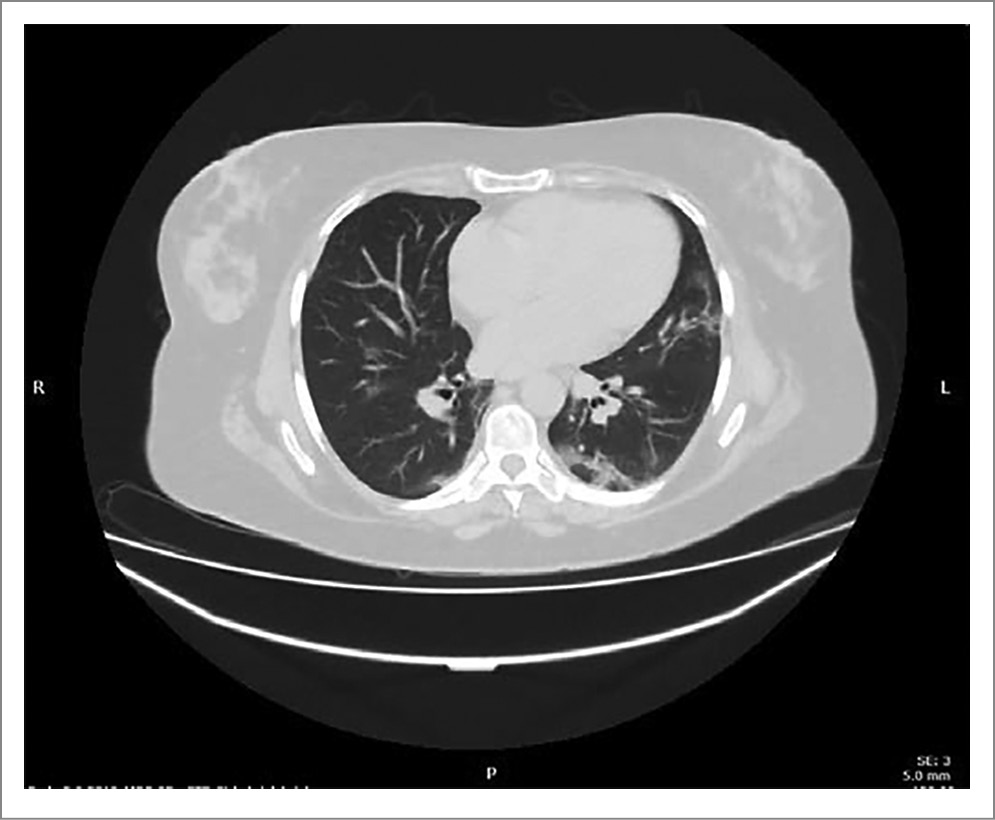

На 14-й день госпитализации выполнена МСКТ органов грудной клетки: отмечалось уменьшение выраженности симптома «матового стекла», с замещением ретикулярными тяжами. По сравнению с КТ на 6-й день госпитализации – положительная динамика (рис. 3).

Рис. 3. Пациентка П. МСКТ органов грудной клетки (14-й день госпитализации).